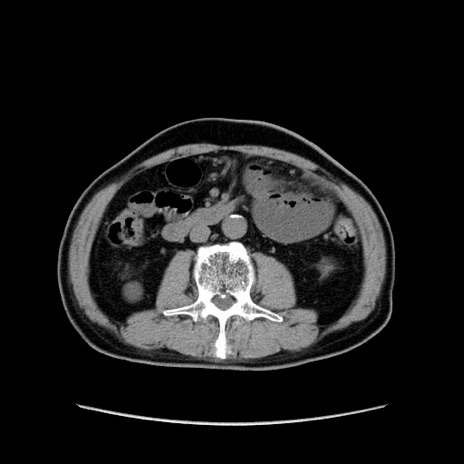

症例24(横断像)

【症例】80歳代男性

【主訴】左側腹部痛、嘔吐

【現病歴】本日早朝より左腹部に痛みあり。昼頃嘔吐認めたため、救急要請。

【既往歴】直腸癌(Mile手術)、胆摘

【身体所見】意識清明、BT 35.9℃、BP 221/93mmHg、SpO2 97%(RA) 、腹部:左ストーマ周囲に限局性の腹部膨隆あり。 膨隆部自発痛・圧痛あり・軟。

【データ】WBC 7700、CRP 0.09